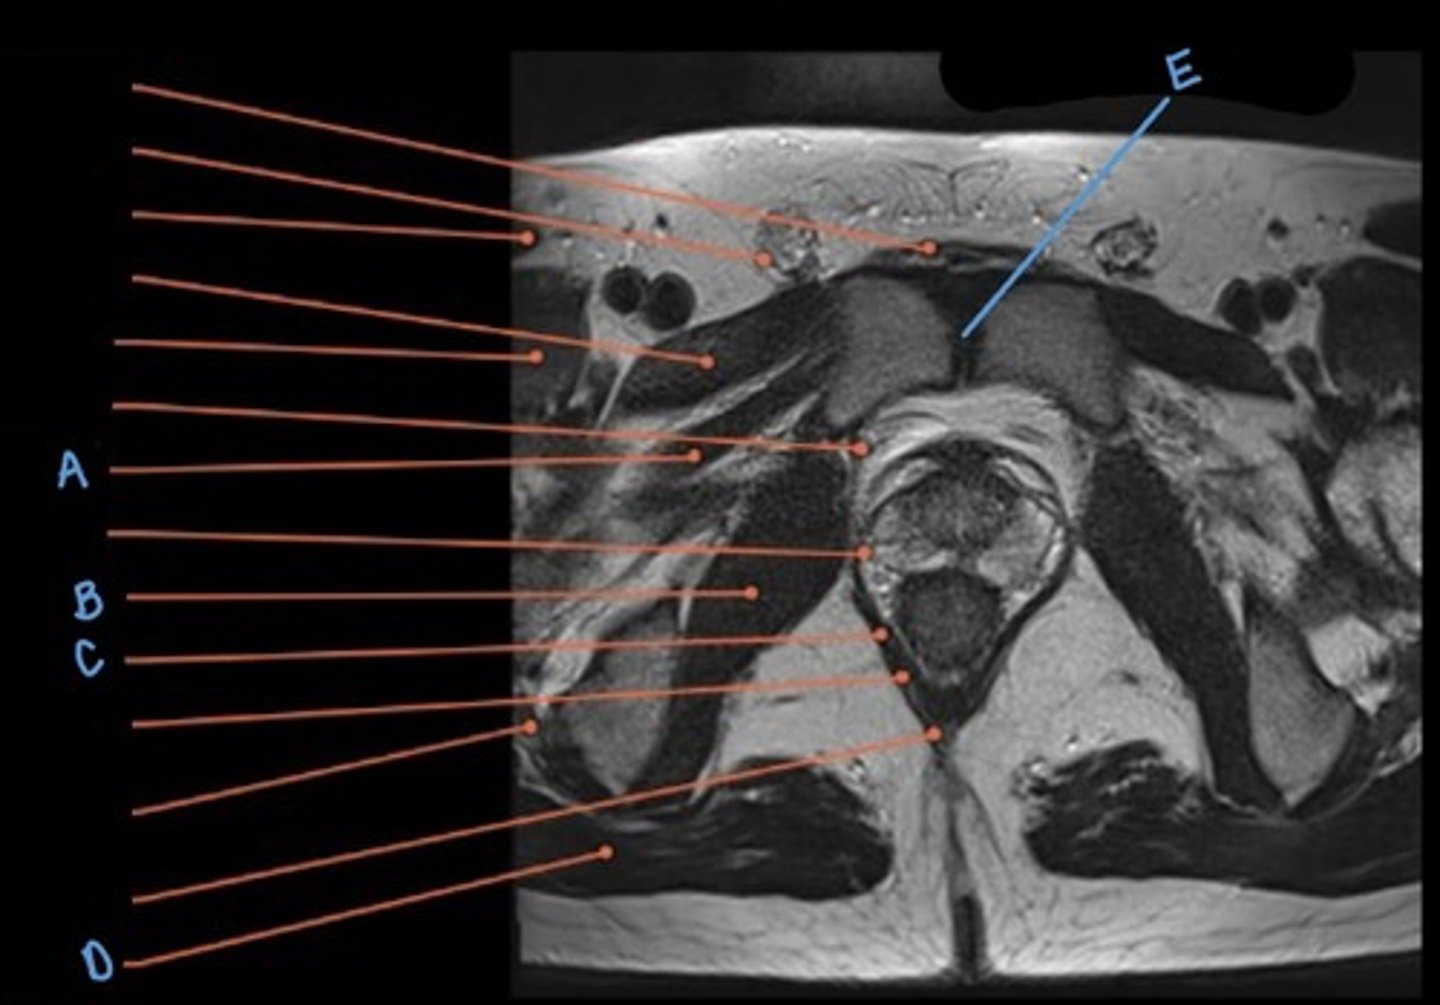

superior pubic ramus

A

rectus abdominus muscle

B

iliopsoas muscle

C

obturator internus muscle

D

rectum

E